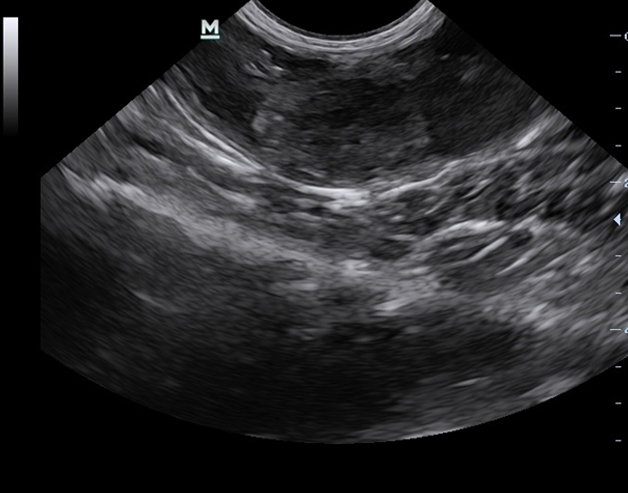

Предварительный диагноз врач ставит после сбора анамнеза и первичного осмотра. Для его

подтверждения необходимо провести УЗИ, сделать биохимический и клинический анализы крови,

исследовать истечения из влагалища.

Диагностика. Для подтверждения диагноза используется УЗИ-диагностика или\и рентген брюшной полости. Для клинического анализа крови характерно наличие лейкоцитоза (увеличение числа лейкоцитов) со сдвигом формулы влево. У части сук и чаще у кошек может выявляться лейкопения (снижение числа лейкоцитов). Так как пиометра является хроническим заболеванием, то часто развивается умеренная нерегенеративная анемия (снижение уровня гемоглобина и снижение гематокрита). Это связано с подавлением функции костного мозга половыми гормонами и имеющимся сепсисом и токсемией.

Для диагностики пиометры применяют вагиноскопическое обследование, осмотр слизистой влагалища, фронтальную рентгенографию, УЗИ матки, пальпацию и другие методы.